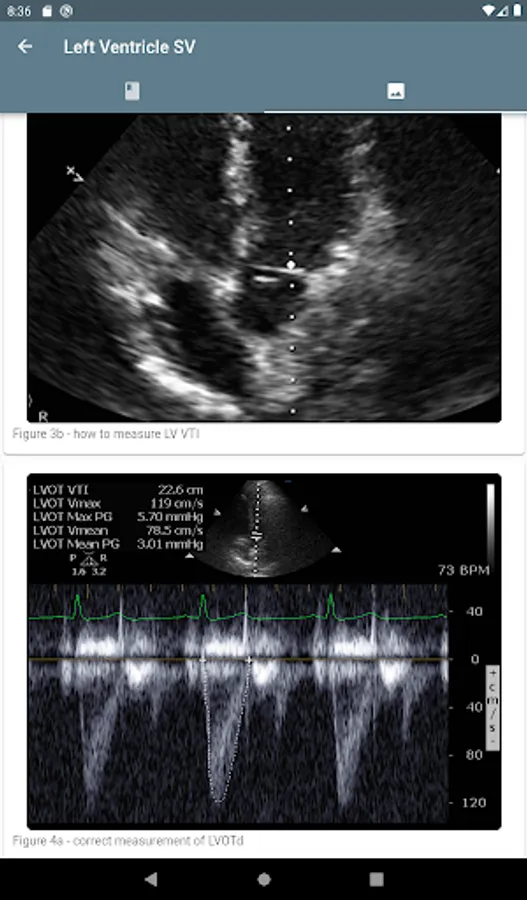

Use the calculators to get the cardiac output, stroke volume, systemic vascular resistance, inferior vena cava respiratory variation, and other metrics. The educational content can be accessed from the calculator so that the learning continues.